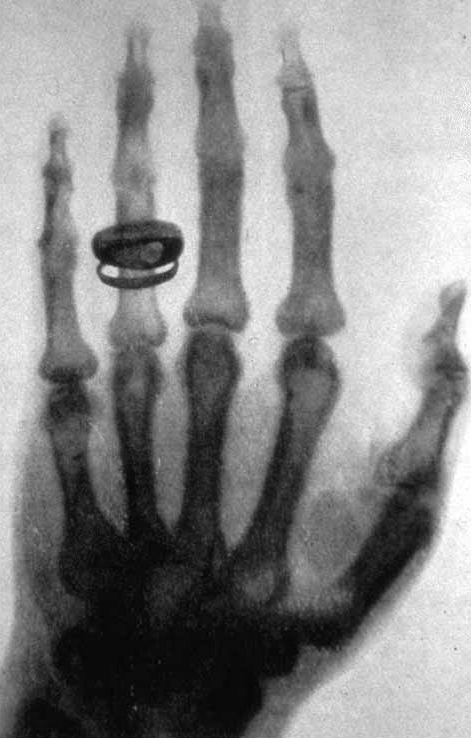

4-3-2 Vi har känt till joniserande strålning sedan slutet av 1800-talet År 1895 upptäckte Wilhelm Röntgen en ny typ av strålning som bildades vid elektriska urladdningar i ett glasrör under vakuum. Strålningen kunde tränga igenom material som vanligt ljus inte kunde gå igenom. Röntgen kallade strålningen för X-strålning och det heter den fortfarande på engelska (X-rays). Röntgenstrålning kallas ofta för den viktigaste upptäckten inom medicinen och Röntgen fick det allra första nobelpriset i fysik, år 1901. Ungefär samtidigt upptäckte Henri Becquerel att salter av grundämnet uran gjorde fotografiska plåtar svarta. Fotografiska plåtar användes för att ta bilder i gamla tiders kameror. Uran skickar ut joniserande strålning som reagerar med den fotografiska plåten som då blir svart. Becquerel hade upptäckt radioaktiviteten och belönades med nobelpriset i fysik 1903. Upptäckterna av röntgenstrålning och radioaktivitet väckte intresse hos andra forskare och snart var det många som forskade om radioaktivitet och joniserande strålning. Under de första 11 år som nobelpris i fysik och kemi delades ut var sex av pristagarna personer som forskade inom joniserande strålning och radioaktivitet. En av forskarna, Marie Curie, belönades med nobelpris i både fysik och kemi under denna period. |

4-3-9 Joniserande strålning är användbar Joniserande strålning har flera egenskaper som gör den användbar. Ett användningsområde är att låta strålning påverka ett material. Det kan handla om sterilisering av sjukvårdsmaterial, tillverkning av nya material eller behandling av sjukdomar. Genom att utsätta en cancertumör för höga strålningsnivåer under kort tid och samtidigt se till att omgivande kroppsvävnad får så lite strålning som möjligt, kan vi få tumören att krympa och slutligen dö. Ett annat användningsområde är att använda strålningen för att undersöka material. Ett exempel är en röntgenundersökning. Material med olika densitet absorberar olika mycket strålning. Om vi bestrålar en arm med röntgenstrålning och har en fotografisk plåt på andra sidan armen går mindre strålning genom själva skelettet än genom den mjuka vävnaden. Det ser därför ut som om vi fotograferar skelettet. Röntgenundersökningar används också i industrin, bland annat för att leta efter sprickor i metallkonstruktioner. Röntgenstrålning kan också användas för att få detaljerad information om strukturen hos material. Genom att studera hur röntgenstrålningen sprids är det möjligt att ta reda på hur atomerna i en kristall sitter. Det går också att bestämma avstånd mellan atomer. Dessa tekniker utvecklas snabbt och för de mest avancerade tillämpningarna behövs så kallat synkrotronljus. ![]() MAX IV-laboratoriet som ligger utanför Lund är ett exempel på en anläggning som kan ge synkrotronljus. Det som skiljer synkrotronljus från vanlig röntgenstrålning är först och främst hur strålningen uppkommer. I synkrotronljuskällan bildas röntgenstrålningen när extremt snabba elektroner böjs av i ett magnetfält. I ett traditionellt röntgenrör uppkommer strålningen när relativt långsamma elektroner träffar ett fast material. ![]() I närheten av MAX IV byggs också European Spallation Source (ESS). Spallation är en process där en tungmetall bombarderas med en protonstråle från en accelerator. Då bildas neutronstrålning. Neutronstrålningen kan användas på ungefär samma sätt som röntgen. Genom att titta på spridningen av neutroner kan forskarna dra slutsatser om ett materials struktur. Neutronspridning är bättre lämpat för organiska material som innehåller många väteatomer. Det betyder att det går att studera material som vatten och organiska ämnen som trä, plast och biologiskt material. |